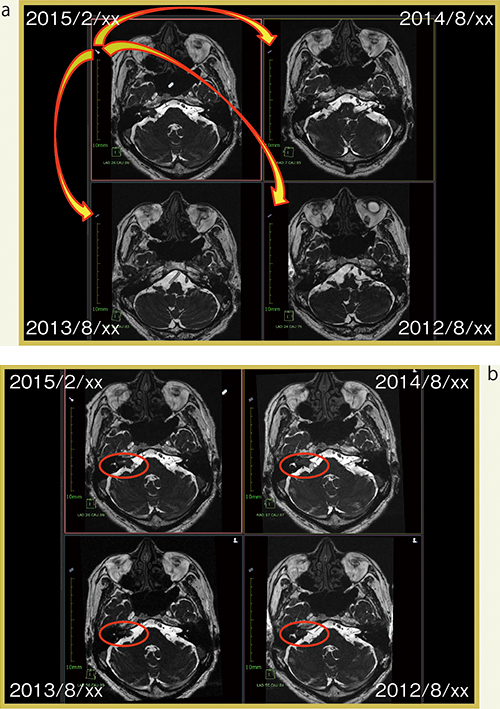

複数回のフォローアップが行われている聴神経腫瘍の症例を紹介する。図3 aは,今回画像と過去3回の検査画像を開いた最初の状態である。今回画像に付いているレジストレーションのアイコンを過去画像にドラッグ&ドロップするだけで,今回画像をキーとして自動で位置合わせが行われる(図3 b)。三次元的に位置合わせされているため,ほかの断面方向でも位置がそろっている(図4)。この症例では,小脳橋角部に突出した囊胞が,時間の経過とともに大きくなっていることがわかる。

図3 AZE Phoenixのボリュームレジストレーション(聴神経腫瘍)

a:レジストレーション前

b:レジストレーション後

図4 図3の症例のコロナル画像